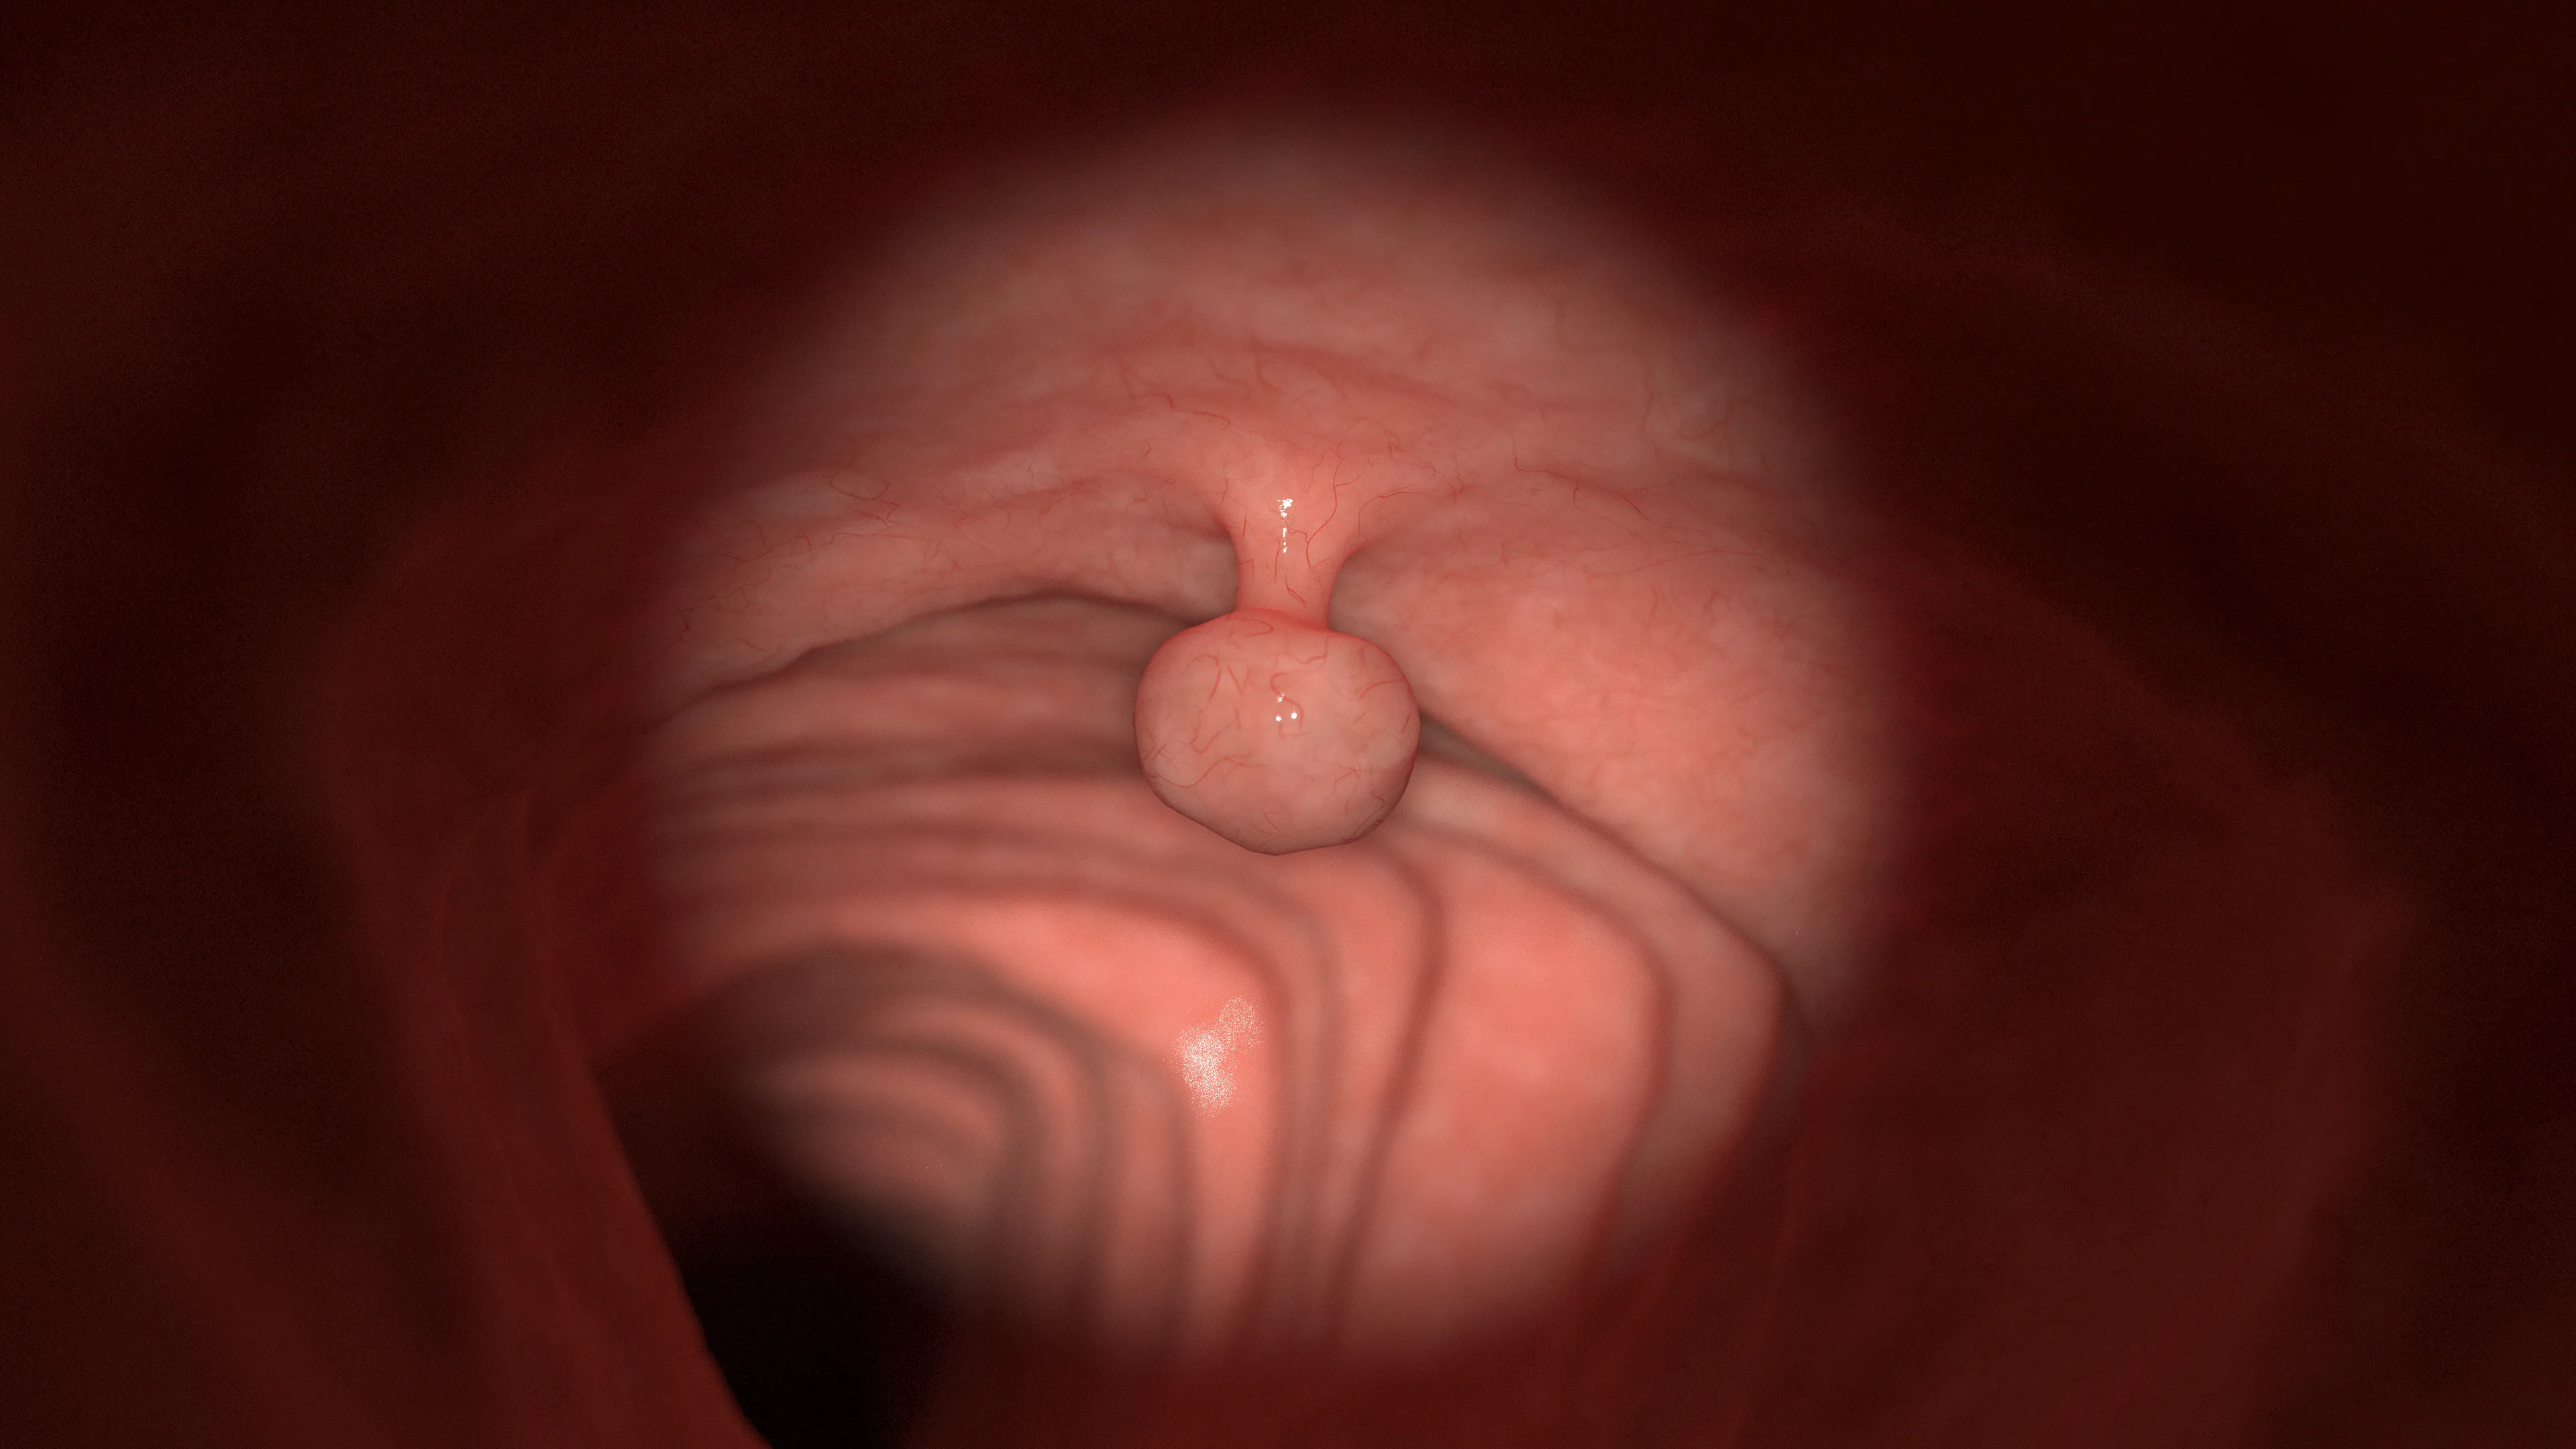

大腸ポリープ

大腸ポリープとは、大腸の粘膜がいぼのように盛り上がった状態を指します。

過形成性ポリープや炎症性ポリープなどいくつかの種類があり、ほとんどが良性ですが、「腺腫性ポリープ」は大腸がんに進行する可能性があるため注意が必要です。

腺腫性ポリープは大腸がんになる一歩手前の状態(前がん病変)とされており、大腸がんの多くが、この腺腫性ポリープから発生することが分かっています。

大きくなるほどがん化リスクが高くなるため、早期の発見・切除が重要です。

大腸カメラ検査では、ポリープの形や大きさ、表面の状態を詳しく観察可能です。

一般的に、5mmを超えるものや不整な形のポリープは、がん化リスクが高いため切除を行います。

初期の大腸ポリープは自覚症状がほぼなく、検査や検診で偶然見つかることがほとんどです。

40歳を過ぎたら、症状がなくても定期的な検査を受け、大腸がんを予防しましょう。

- 初期段階……ほとんど無症状

- 大きくなった場合……便秘、下痢、腹痛、血便など